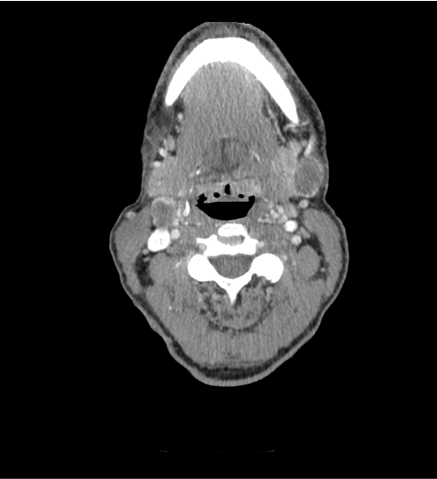

TC cervical y torácica

HALLAZGOS RADIOLÓGICOS